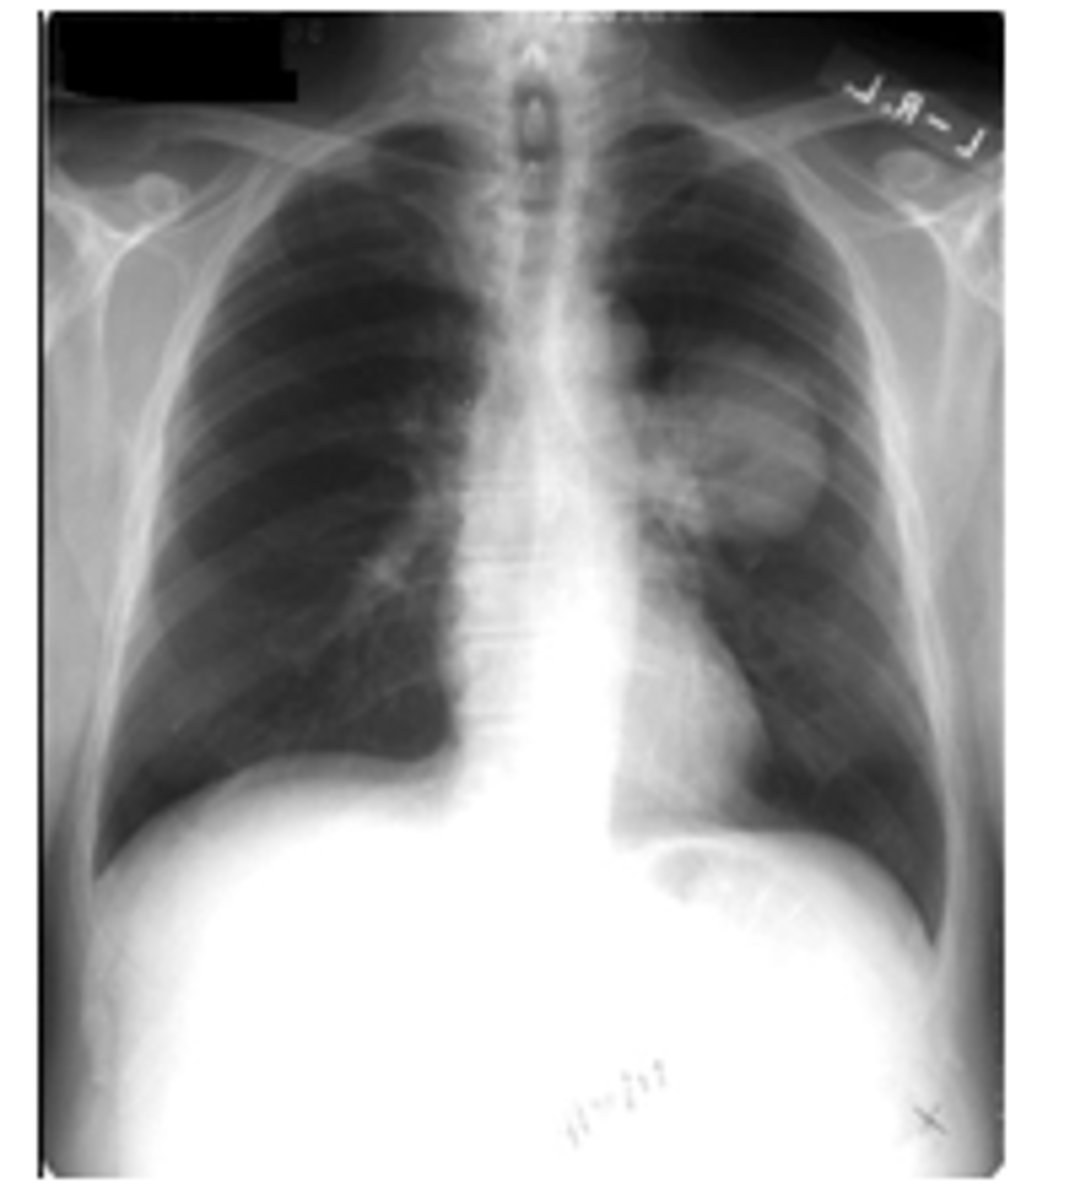

ID picture on back

LLL pneumonia

<p>LLL pneumonia</p>

What 2 patterns can community acquired pneumonia appear as? Typical patterns of bacterial, viral, mycoplasma and conolidation

Alveolar or interstitial

oBacterial – usually alveolar and focal

oViral and mycoplasma– usually interstitial and diffuse

oA consolidation = severe alveolar infiltrate